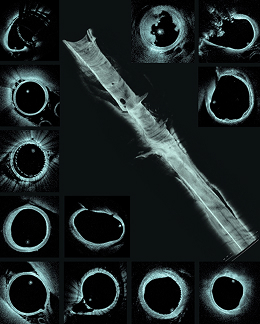

Intravascular optical microscopy provided by nOCT can offer unique insights into the treatment of brain aneurysms, ischemic stroke, and atherosclerotic intracranial disease by revealing details of the vessel wall and devices that remain hidden from non-invasive imaging modalities.

nOCT images vessels, disease and other important structures at >10x the resolution of today’s imaging systems and improving clinicians’ understanding of neurovascular disease.

Clot sitting on the struts of the flow diverting stent, not visible with traditional non-invasive imaging like angiography and Cone beam CT.